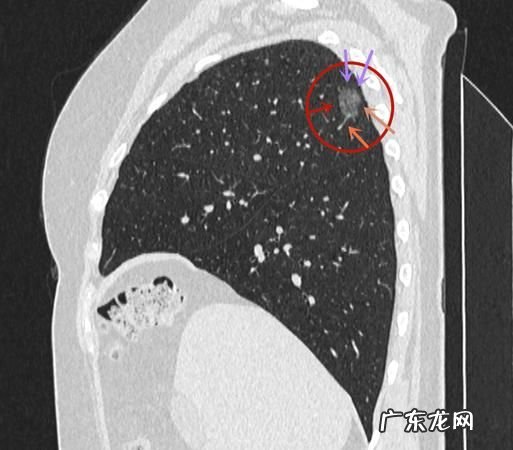

王先生没有抽烟习惯 , 所以一直对自己的肺很有信心 , 结果在体检时发现有肺结节 , 他一开始不相信,马上去医院做了进一步的肺部CT,结果还是确诊了,而且是纯磨玻璃结节 。

结节不大,直径只有4毫米,虽然是磨玻璃结节,但医生还是建议他回去休养,暂时不做任何处理 。

王先生回去后休养了一年多,期间非常注意身体健康 , 与亲友相见时都提示对方不要抽烟,以防二手烟影响,结果一年后再复查,结节不减反增,直径达到4.2毫米了 。